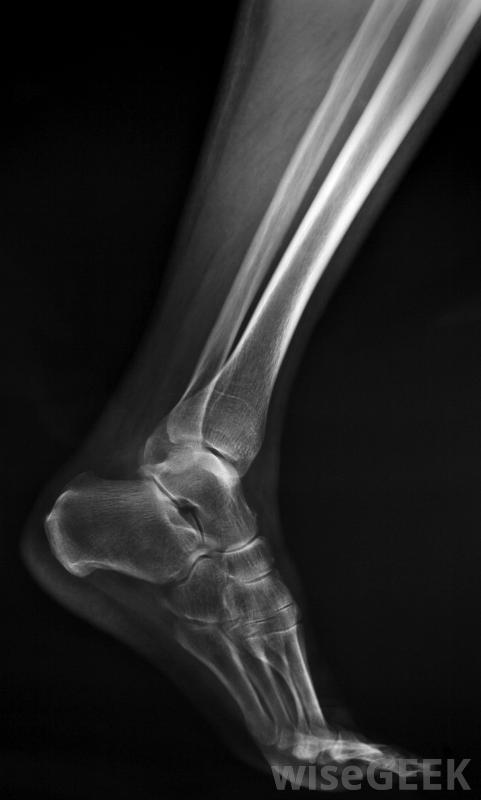

腓骨比胫骨更薄、更脆弱。腓骨也被称为腓骨之一,位于外侧,或者小腿外侧。这么长,细骨钩在胫骨上,从膝盖下方一直延伸到脚踝。它与较重的相邻胫骨的连接方式使这两块骨头看起来像一个钩子或安全销。尽管胫骨承受着身体的重量,并且在某种程度上独立于腓骨,但较厚的骨头的骨折可能会造成损害腓骨也是。腓骨不承受重量,固定一个腓骨板可以为该骨提供必要的额外支撑,以确保正常愈合。

腿部将使用石膏在放置腓骨板之后如果骨骼"固定"不正确,骨骼稳定性的破坏会导致持续的、可能是永久性的疼痛和功能障碍。在许多闭合性骨折中,骨折碎片不会穿透皮肤,在负重限制的情况下使用石膏几周,可以使骨头愈合。像腓骨这样的骨头附着在更坚固的骨头上而不负重,外科植入腓骨板有助于保持骨的位置,同时将骨折端固定在一起,以提高正常愈合的机会。

通常需要在术后数周内进行铸造和休息已放置腓骨钢板。腓骨钢板的放置取决于骨折的位置和严重程度。换句话说,整个腓骨或仅部分腓骨可能涉及到钢板技术用于腓骨板的薄金属条与骨平行放置,并直接拧入骨中。然后在腿外侧放置石膏,持续数周,以确保腿保持不动。在许多情况下,即使完全愈合,腓骨板仍与骨钩连在一起

一些腿部骨折可能需要钢板、螺钉或杆,以确保它们能够正确对齐愈合。